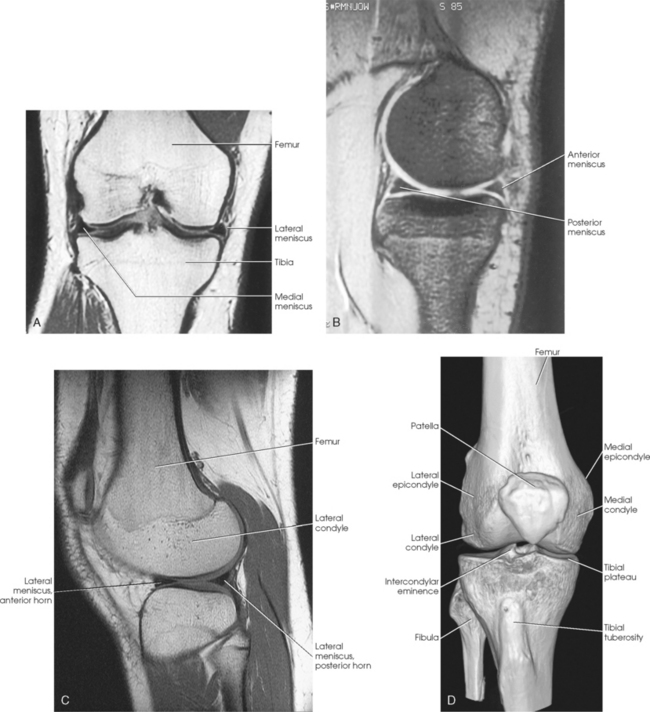

The knee joint contains two fibrocartilage disks called the lateral meniscus and medial meniscus (Fig. 6-10; see Fig. 6-9). The circular menisci lie on the tibial plateaus. They are thick at the outer margin of the joint and taper off toward the center of the tibial plateau. The center of the tibial plateau contains cartilage that articulates directly with the condyles of the knee. The menisci provide stability for the knee and act as a shock absorber. The menisci are commonly torn during injury. Either a knee arthrogram or a magnetic resonance imaging (MRI) scan must be performed to visualize a meniscus tear.

Fig. 6-11 A, Axial CT scan of foot and calcaneus. B, MRI coronal plane of knee joint. Joint spaces are clearly shown.